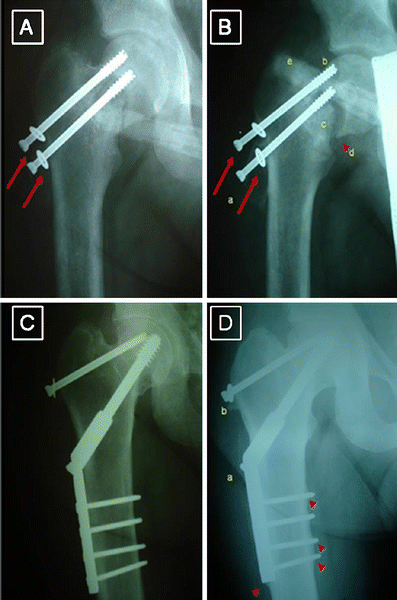

a Three weeks post-op. Radiological signs of loosening of the Asnis screws are obvious due to resorbtion at the fracture site. b Twenty weeks post-op. The screws are further loosened (arrows, a) and cut out of the screws is obvious (b). The femoral head is in varus displacement (arrowhead, d) and its margins were sclerotic (c). No radiological signs of necrosis of the femoral head are apparent. The peritoneal lavage hose projects on the major trochanter (e). c Revisional procedure of the fracture non-union. The femoral head is fixed in valgus orientation with a dynamic hip screw (DHS—Richards type) plus an antirotator cannulated Asnis Screw. d The latest follow-up, 2 years after the secondary osteosynthesis procedure. The fracture is fully united with sufficient callus formation (arrowheads). No signs of malposition, progression of valgus impaction or deterioration are evident. The screws are in place without any signs of loosening (a, b). The femoral head shows no radiological signs of deterioration or osteonecrosis

Three months after the secondary procedure the fracture united and although the femoral head contour showed minor irregularities no significant radiological signs of osteonecrosis or osteoarthritis were apparent.

At his latest follow-up, 2 years after the secondary osteosynthesis procedure, the fracture has fully united with sufficient callus formation and without progression of valgus impaction. The screws are in place without any signs of loosening. The viability of femoral head shows no radiological signs of deterioration and the patient has no clinical signs of osteonecrosis. In fact he has an excellent Harris Hip Score and enjoys full outdoor activity (Fig. 2d).